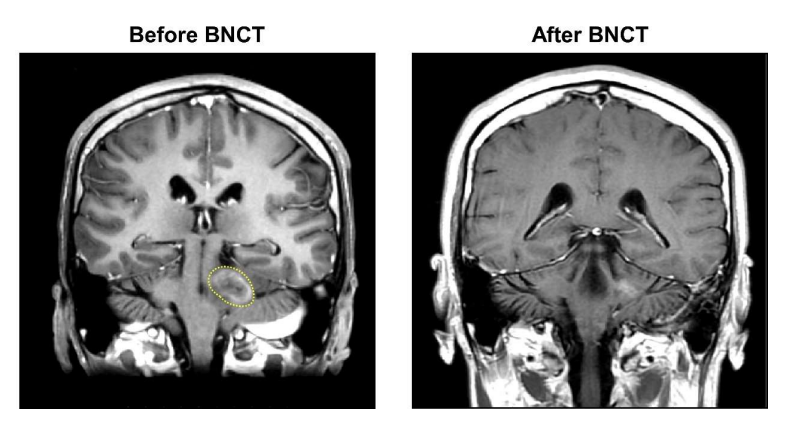

患者為49歲白人女性,2016年診斷為毛細(xì)胞型星形細(xì)胞瘤(WHO I級(jí))。2018年病理診斷提示間變性,在手術(shù)以及多種放化療方案失敗后,2019年轉(zhuǎn)至臺(tái)北榮總。經(jīng)檢查,該患者腦干上方處腫瘤復(fù)發(fā)(圖2A),并進(jìn)展為多形性黃色星形細(xì)胞瘤(WHO II級(jí)),符合緊急和同情使用原則。按計(jì)劃進(jìn)行兩次BNCT治療,18F-BPA-PET結(jié)果顯示,第一次BNCT的T/N和T/B值為2.46和2.87,第二次BNCT的T/N和T/B值為2.34和2.39。第一次BNCT的平均、最小和最大腦腫瘤劑量分別為6.79、5.42和9.16 Gy-E。第二次BNCT的平均、最小和最大腦腫瘤劑量分別為6.62、5.81和8.01 Gy-E。在第1次、第2次BNCT治療中,血硼濃度分別為41.13 ppm和27.41 ppm。未觀察到嚴(yán)重急性或晚期毒性反應(yīng)。隨訪顯示,患者達(dá)到了PR(圖2B),至今未復(fù)發(fā)。在接受兩次BNCT后,目前患者存活超過662天。

圖2:腫瘤縮小的MRI圖像,A為BNCT治療前,B為BNCT治療后。黃色虛線處代表腫瘤。